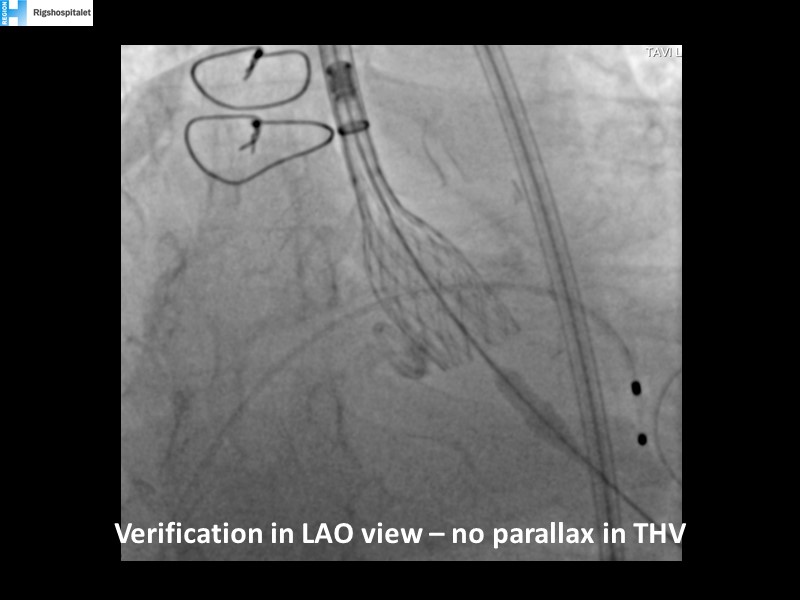

Your most challenging TAVI cases - Achieving precision and control with Evolut platform

How to deal with challenging anatomies? Find answers in this EuroPCR 2022 session with case studies to explore and learn how to achieve optimal patient outcomes with Evolut platform, uncover practical tips and techniques to achieve implant precision and control, and become familiar with technical considerations and procedural execution of TAVI.